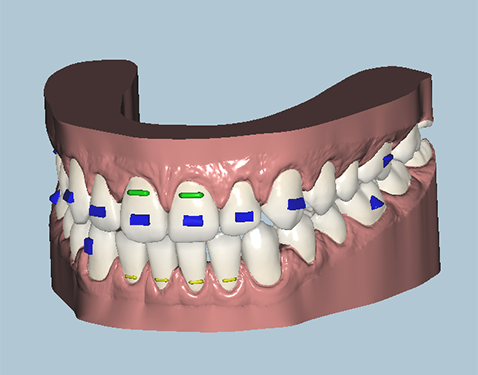

Orthodontist Proposal

After all materials are gathered, an orthodontist creates the movement proposal for the doctors approval. This is done through an on-line link that can be viewed in each stage of the process in 3D. Changes can be requested as needed or the proposal is approved for production.

Placeholder Picture